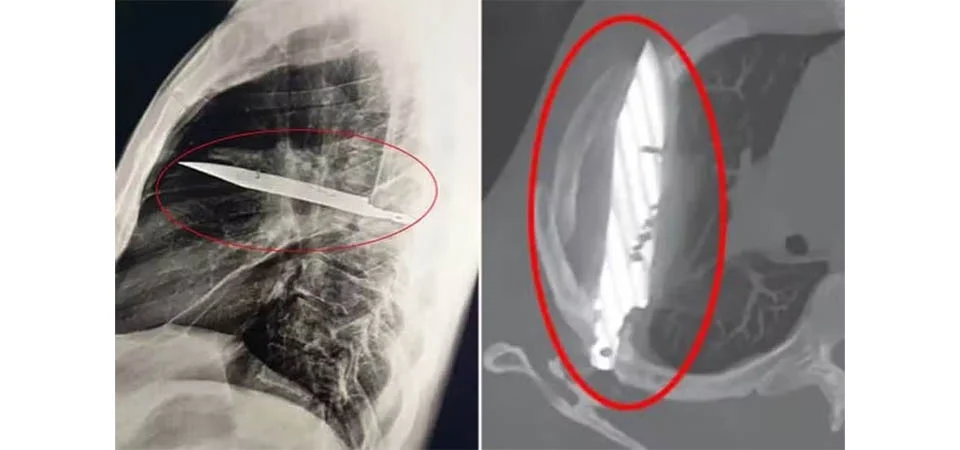

Um médico ficou chocado ao ao descobrir que um homem de 44 anos vivia com uma faca alojada no peito há oito anos, após ir a uma consulta reclamando de...